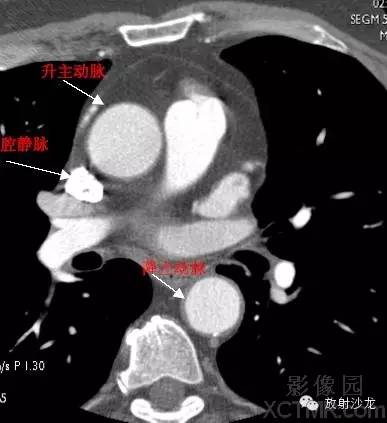

A.Aorta-Ascending Aorta升主动脉

SVC –Superior Vena Cava上腔静脉

PA -Pulmonary Artery肺动脉